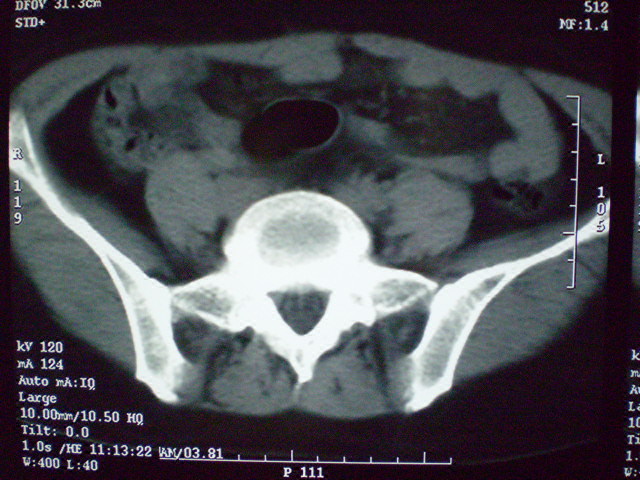

f 60y,b超提示脂肪瘤.[img][/img]

右侧附件囊性畸胎瘤,三种组织均见.

那个高密度灶形状好象牙齿。典型,收藏了

脂肪密度肿块,内可见团块状影,典型皮样囊肿

的确比较典型的畸胎瘤!不过,应该确切的说是盆腔畸胎瘤,右侧附件来源的可能性比较大。